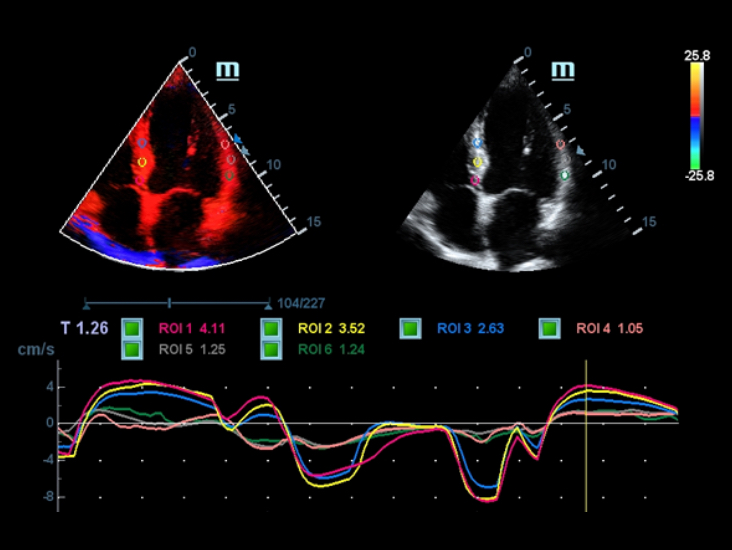

Berbagai macam alat bantu aplikasi: menjamin akurasi dengan kenyamanan iTouch

DC-40 dengan Full HD menghadirkan berbagai macam alat bantu yang memaksimalkan akurasi diagnostik dengan kenyamanan. Mencakup Pencitraan Umum, OB/GYN dan Kardiologi, DC-40 dengan Full HD bisa menghadirkan solusi lengkap bagi aplikasi klinis umum/mainstream, dengan alur kerja yang disederhanakan demi memastikan efisiensi.

Smart Track

Smart Track menyediakan optimasi yang cepat dan cerdas untuk pencitraan vaskular dengan operasi satu sentuhan yang sederhana. Alat ini bisa mengoptimalkan spektrum Warna, Daya, dan PW dengan melakukan pelacakan mandiri dan mengurangi langkah-langkah yang menghabiskan waktu. Oleh karena itu, alur kerja pemeriksaan vaskular disederhanakan dengan tampilan yang optimal.